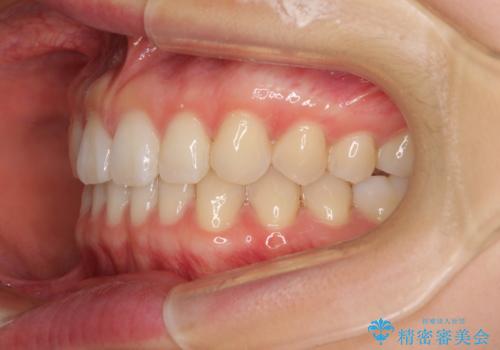

インビザラインによるすきっ歯の改善

- 上の前歯の隙間を気にして来院された患者様です。

インビザラインにより、隙間を閉じながら、隙間の原因であるディープバイトを改善していくこととしました。